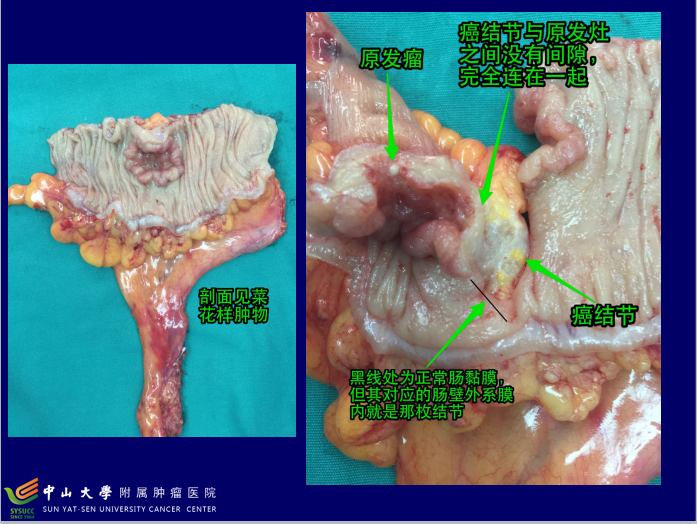

结直肠癌(colorectal cancer,CRC)是我国最常见的消化道恶性肿瘤之一,而且发病率和死亡率呈上升趋势。了解结直肠癌的分期旨在掌握其发展状况,以便指导制定治疗计划及评估预后。中山大学肿瘤医院(结直肠外科)陈功教授为您讲解CRC临床病理分期的几个问题。